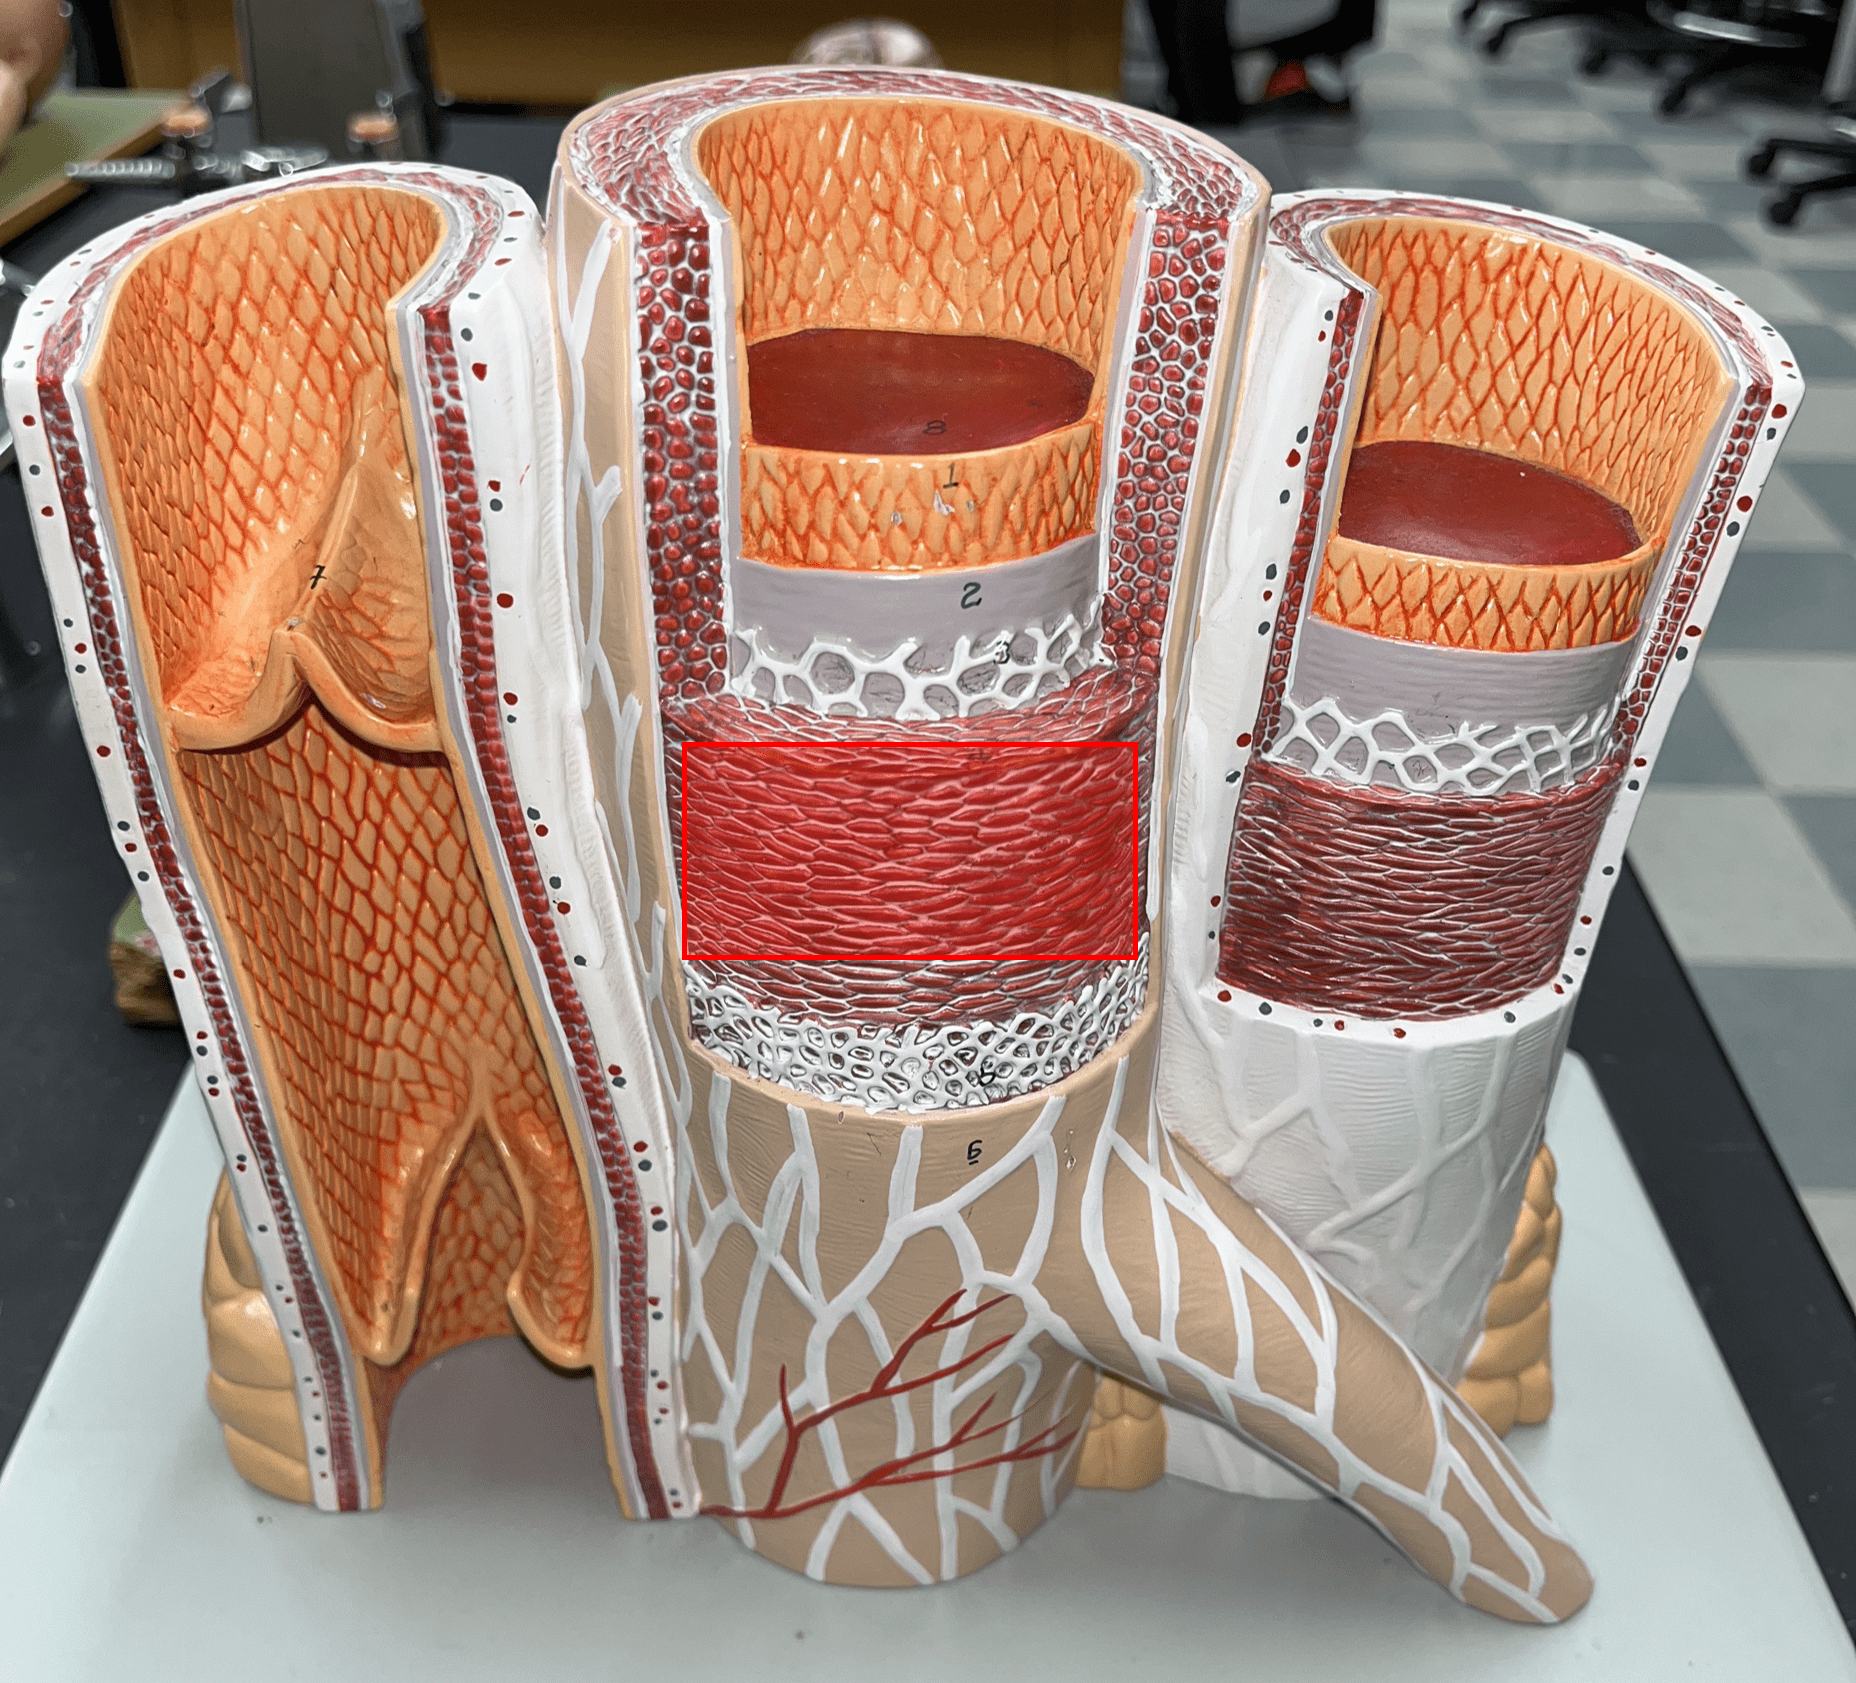

tunica media

• The middle layer of an artery wall.

• Composed of smooth muscle and elastic fibers.

• The smooth muscle allows for vasoconstriction and vasodilation.

• Composed of smooth muscle and elastic fibers.

• The smooth muscle allows for vasoconstriction and vasodilation.